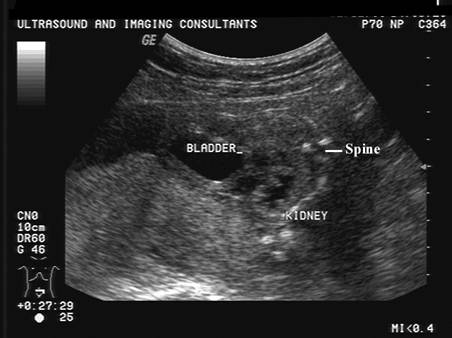

- Enlarged bladder (which

does not appear to change during the scan suggesting urethral

obstruction).

- Single kidney or severely

dysplastic kidney (2).

- Urethral obstruction /

atresia (2).

- Oligohydramnios.

- Megacystis.

- Megaureter.

- Renal obstruction.